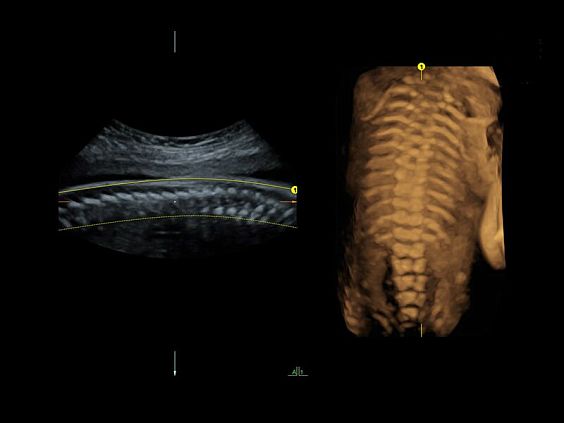

• Программа 3D и режим инверсии (при наличии специализированных датчиков)

• Advanced 4D - расширенный пакет 4D для механических объемных датчиков RM6C, RIC5-9, RIC6-12, RSP6-16:

• Режим 4D - трехмерное сканирование в реальном масштабе времени

• Томографический ультразвук (TUI)